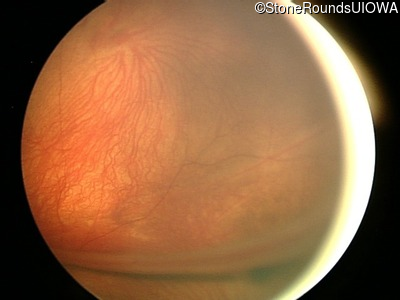

Fundus Photography - Left - 20/300

Exemplar